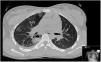

She completed empirical treatment with ampicillin and clindamycin for 10 days. Thoracic pain improved gradually and she remained asymptomatic and was discharged to adolescent consultation. Follow-up CT performed 3 months after the episode demonstrated a complete resolution of the pulmonary changes seen in the previous study (Fig. 2).